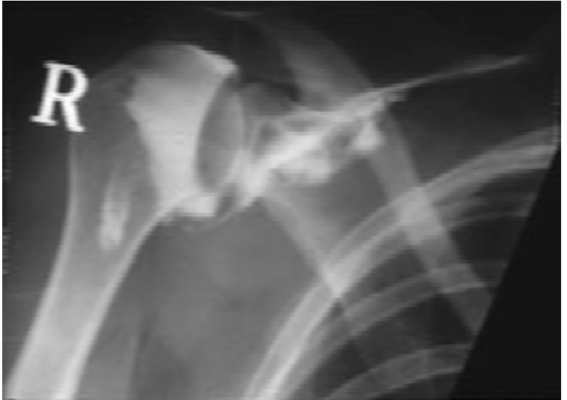

Mặc dù chụp X quang thường bình thường, nhưng chúng rất quan trọng để loại trừ các nguyên nhân khác và đánh giá tình trạng thoái hóa khớp và trật khớp. Phát hiện phổ biến nhất trên hình ảnh X quang là giảm mật độ xương do không sử dụng.

X quang khớp vai cản quang trong viêm dính khớp vai với hình ảnh co rút khoảng khớp. Ghi chú mất khoang túi nách (axillary recess) và giảm lượng chất cản quang được tiêm.